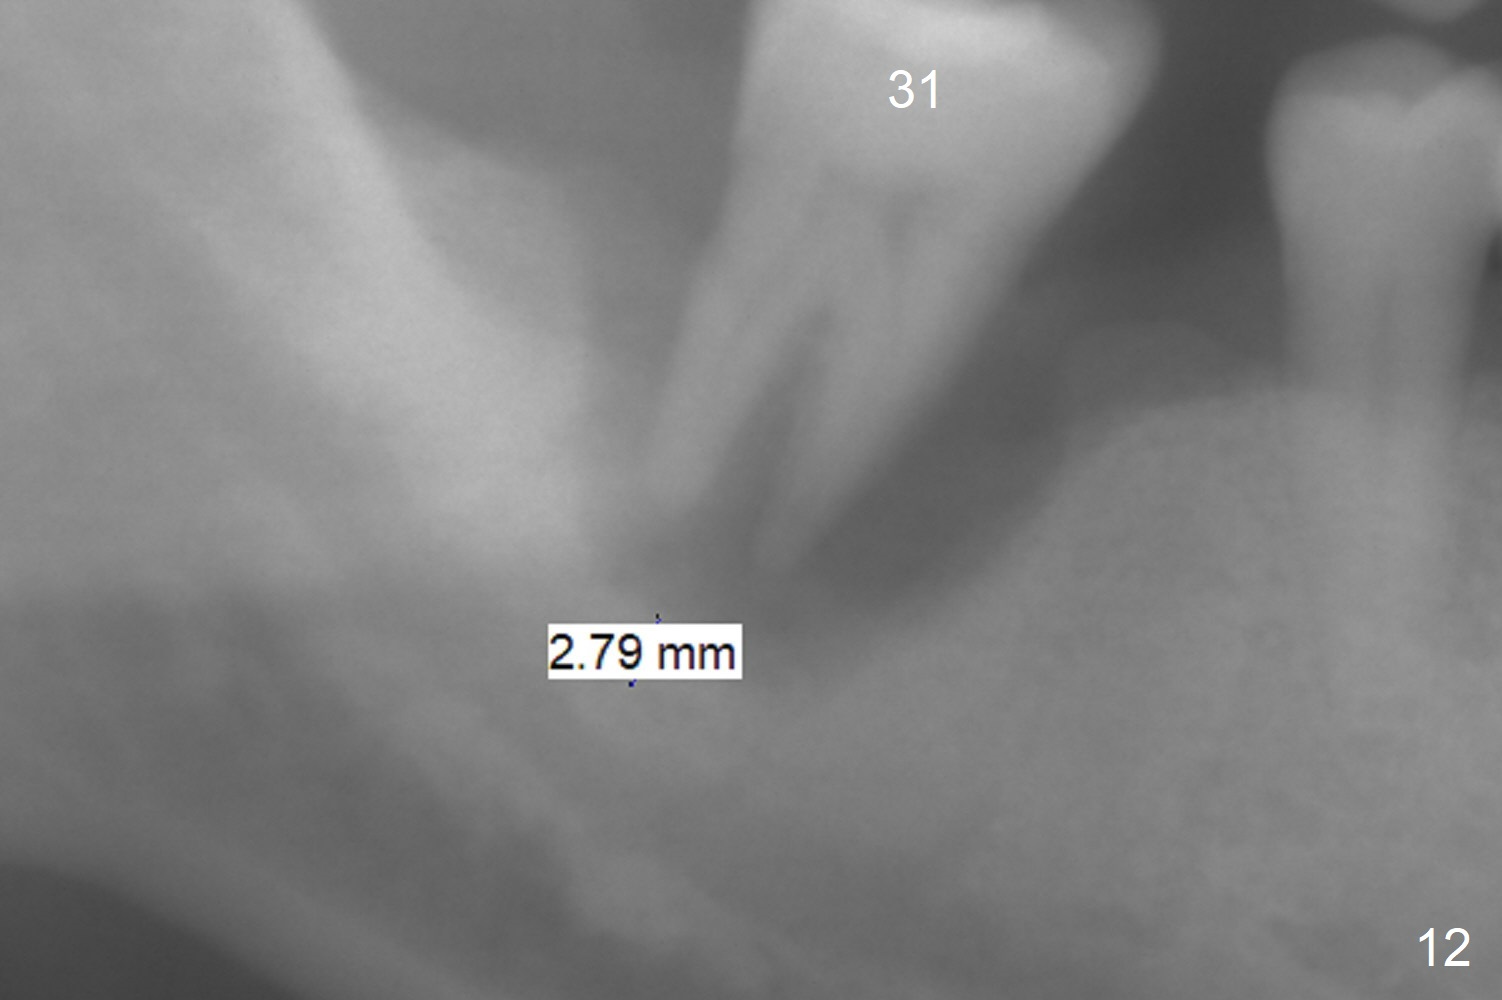

Prepare 3 large pieces of gauze with the vasoconstrictor. If one of them is still too small for the socket, insert another piece of gauze without the vasoconstrictor for pressure hemostasis. Prepare PRF (x4) and Sinus Master Kit in case short stoppers are needed (Fig.12). CBCT taken immediately preop shows relatively wide ridge at #30 (Fig.14,16). The implant at #31 should be place in the distobuccal aspect of the socket (Fig.15,17): 2 mm drill with 7 mm stopper, 2.8 mm round drill at 5 mm (50 RPM) and 3.6 mm at 3 mm.